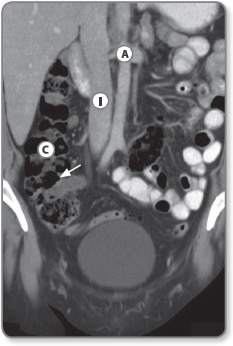

Colon

The colon starts at the caecum, where it communicates with the terminal ileum via the ileocaecal valve, and extends clockwise 1.5 m around the abdomen to the rectum. The colon is larger in diameter and more fixed in position than the small intestine, and has characteristic small pouches, called ‘haustra’, caused by sacculations (folding) of the colonic wall. The caecum is located in the right iliac fossa (Figure 1.12). The ileocaecal valve is usually on the posteromedial wall of the caecum, and the appendix approximately 2 cm below the valve.

The ascending colon is located along the right flank and continues as the transverse colon, which crosses the abdomen and then descends along the left lumbar region to the left iliac fossa.

Figure 1.12: Coronal CT image showing the ascending colon Ⓒ and the ileocaecal junction (arrow). The aorta Ⓐ and inferior vena cava Ⓘ are seen in the midline along with small bowel loops in the left side Ⓛ of the abdomen.

The ascending and descending portions of the colon are retroperitoneal and therefore fixed in position. Conversely, the transverse colon, caecum and sigmoid colon are attached to their respective mesocolon (a double layer of peritoneum) and hang freely within the abdominal cavity. Therefore, these segments may be tortuous or mobile. At the left iliac fossa the colon becomes more tortuous as it forms the sigmoid colon. It enters the pelvis and descends along the posterior wall and presacral space, to form the rectum and anal canal.